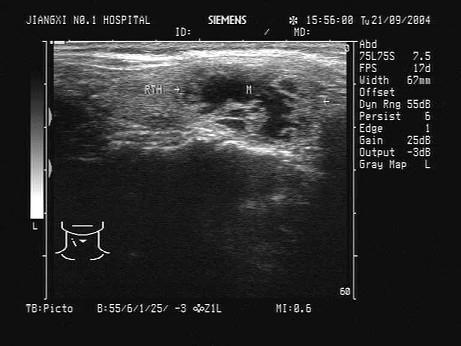

问题 患者感颈部肿胀1年余。根据超声声像图,诊断为?(?)

选项 A.多发腺瘤 B.结节性甲状腺肿并囊变 C.甲状腺囊肿 D.甲状腺癌 E.甲状腺炎

答案 B